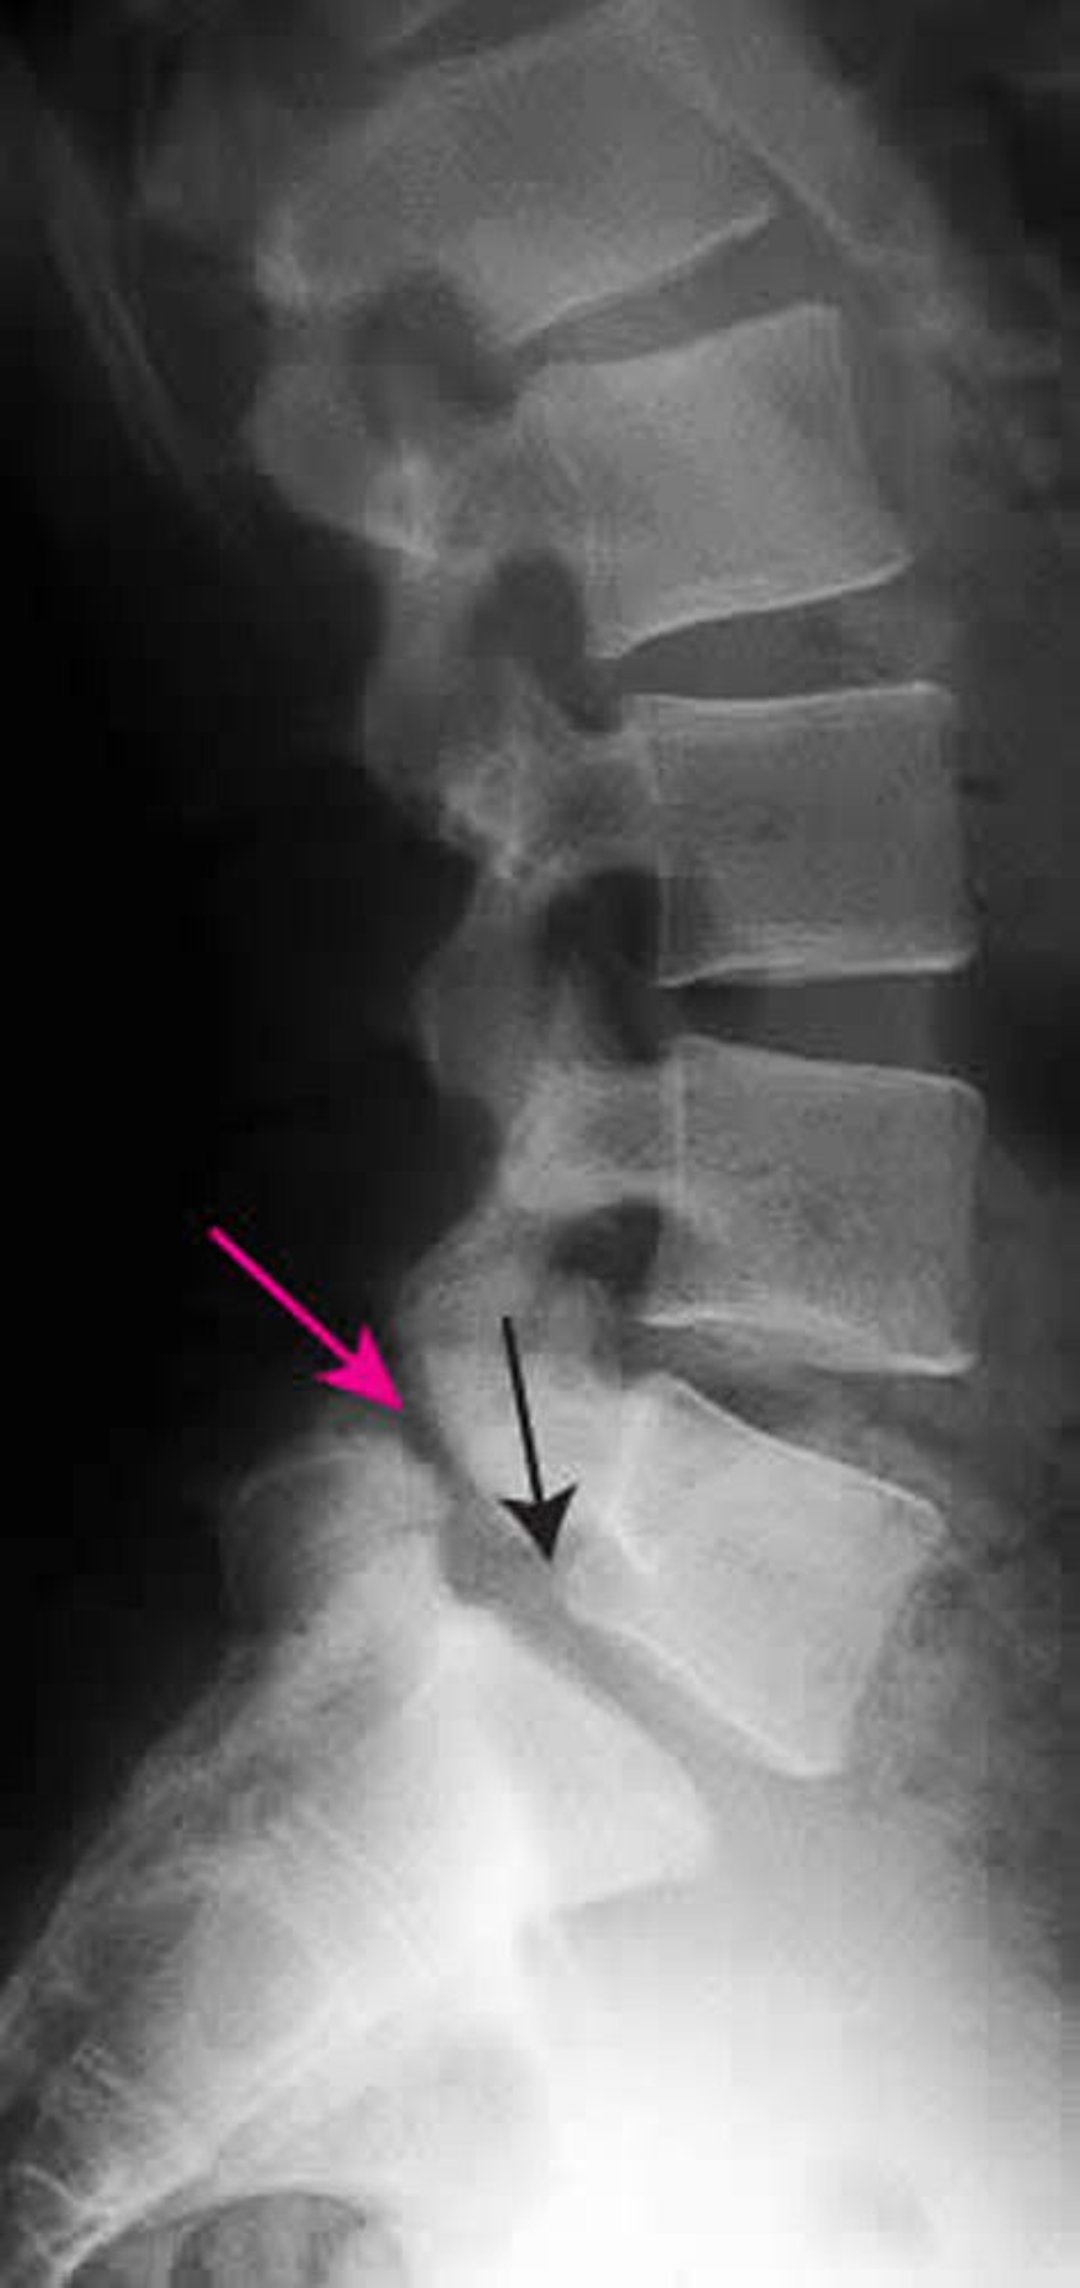

Phim chụp X-quang này cho thấy tình trạng trượt đốt sống độ 1 của đốt sống L5 trên đốt sống S1. Mũi tên màu đen cho thấy đường viền sau của L5 trượt ra trước so với S1. Mũi tên đỏ chỉ vào trượt đốt sống (khuyết tật trong mỏm gai).

ZEPHYR/THƯ VIỆN HÌNH ẢNH KHOA HỌC